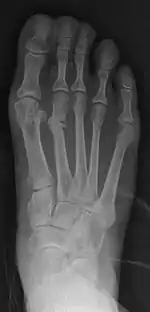

شکستگی تنشی استخوان(به انگلیسی: Stress fracture) یا Fatigue Fracture شکستگی ناکامل استخوان است که در اثر نیروهای کم ولی تکرار شونده و در اثر خستگی استخوان اتفاق میافتد.

این شکستگی اغلب در اندام تحتانی و به صورت شکستگی خطی و ترک خوردگی است. محل شایع آن در استخوان درشت نی و استخوانهای کف پا بخصوص استخوانهای کف پایی دوم و سوم است و در ورزشکاران و دوندهها زیاد اتفاق میافتد. شیوع آن در ورزشکاران زن ۶۴ درصد و در مردان ۵۰ درصد میباشد. وقوع این شکستگی در اندام فوقانی بسیار کمتر از اندام تحتانی است و در بازیکنان تنیس و بیسبال دیده میشود. اکثراً در مواقعی که شخص، فشار زیادی به اندام وارد میکند یا در مواقعی که ورزشکار مقدار تمرین را بهطور غیرمعمول افزایش میدهد، بروز میکند.[1][2]

تشخیص توسط معاینه پزشک و انجام پرتونگاری میسر است، ولی یافتههای آن معمولاً دیر ظاهر میشوند. گاهی لازم است برای تأیید تشخیص یا تشخیص افتراقی از بیماریهای دیگر استخوان، اسکن استخوان انجام شود.[1]